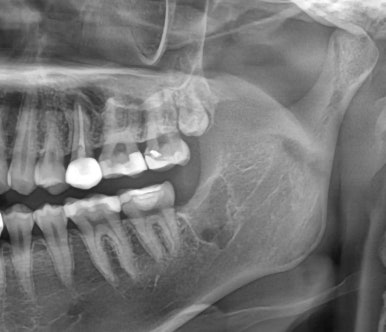

📌 사랑니 발치 실제 사례

최근 내원한 20대 여성 환자분은

좌측 아래 사랑니 부위에 통증이 반복되어 내원하셨습니다.

| 발치 전 | 발치 후 |

CT 검사 결과,

사랑니는 똑바로 있었지만 맹출 공간이 부족해

기능적 활용이 어려운 상태였고,

결국 발치를 결정하셨습니다.

수술은 국소마취로 약 10분 만에 마무리되었고,

현재는 빠르게 회복 중입니다 😊